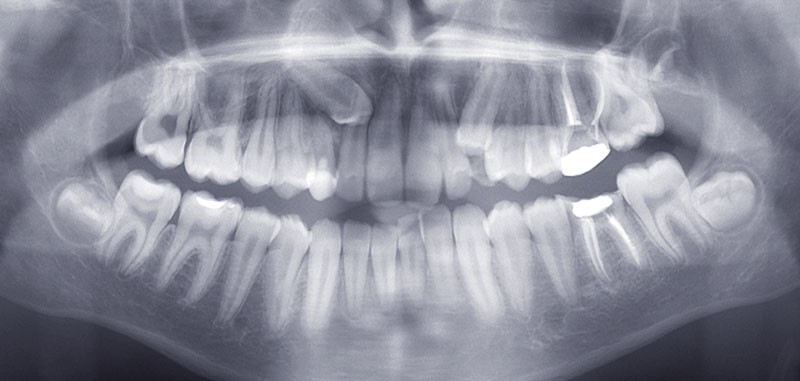

Examen radiographique

La reconstruction 3D confirme la position vestibulaire de la 13 avec appui coronaire sur la racine de 12 (fig. 8 et 9).

Le bilan rétro-alvéolaire révèle une atteinte du plancher radiculaire de 26 et 36 (fig. 10 et 11).

Le tracé céphalométrique confirme la dysmorphie squelettique ainsi que le contexte dento-alvéolaire (fig. 12).